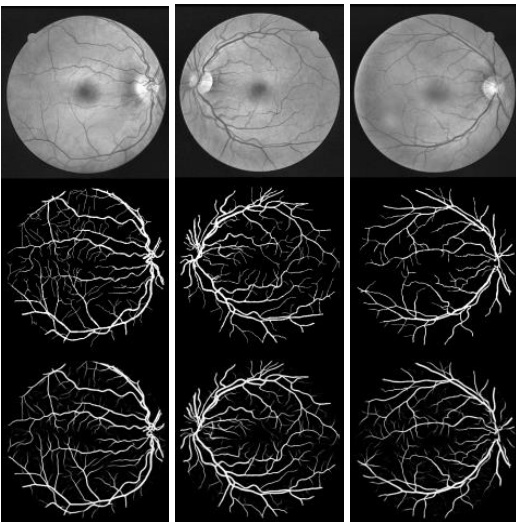

Fig. 6. Example images from training dataset: left column from DRIVE dataset, middle column from STARE dataset and right column from CHASE-DB1 dataset. The first row shows the original images, second row shows fields of view (FOV), and third row shows the target outputs.

图 6: 训练数据集示例图像:左列来自DRIVE数据集,中间列来自STARE数据集,右列来自CHASE-DB1数据集。第一行显示原始图像,第二行显示视场 (FOV) ,第三行显示目标输出。

To demonstrate the performance of the RU-Net and R2U-Net models, we have tested them on three different medical imaging datasets. These include blood vessel segmentation s from retina images (DRIVE, STARE, and CHASE_DB1 shown in Fig. 6), skin cancer lesion segmentation, and lung segmentation from 2D images. For this implementation, the Keras, and TensorFlow frameworks are used on a single GPU machine with 56G of RAM and an NIVIDIA GEFORCE GTX-980 Ti.

为了展示RU-Net和R2U-Net模型的性能,我们在三个不同的医学影像数据集上进行了测试。这些数据集包括视网膜图像中的血管分割(如图6所示的DRIVE、STARE和CHASE_DB1)、皮肤癌病变分割以及2D图像中的肺部分割。本次实现使用了Keras和TensorFlow框架,运行在配备56G内存和NVIDIA GEFORCE GTX-980 Ti单GPU的机器上。

We have experimented on three different popular datasets for retina blood vessel segmentation including DRIVE, STARE, and CHASH_DB1. The DRIVE dataset is consisted of 40 color retinal images in total, in which 20 samples are used for training and remaining 20 samples are used for testing. The size of each original image is $565\times584$ pixels [44]. To develop a square dataset, the images are cropped to only contain the data from columns 9 through 574, which then makes each image $565\times565$ pixels. In this implementation, we considered 190,000 randomly selected patches from 20 of the images in the DRIVE dataset, where 171,000 patches are used for training, and the remaining 19,000 patches used for validation. The size of each patch is $48\times48$ for all three datasets shown in Fig. 7. The second dataset, STARE, contains 20 color images, and each image has a size of $700\times605$ pixels [45, 46]. Due to the smaller number of samples, two approaches are applied very often for training and testing on this dataset. First, training sometimes performed with randomly selected samples from all 20 images [53].

我们在三个不同的视网膜血管分割常用数据集上进行了实验,包括DRIVE、STARE和CHASH_DB1。DRIVE数据集共包含40张彩色视网膜图像,其中20个样本用于训练,剩余20个样本用于测试。每张原始图像的尺寸为$565\times584$像素[44]。为构建方形数据集,图像被裁剪为仅保留第9至574列的数据,使每张图像变为$565\times565$像素。本实验中,我们从DRIVE数据集的20张图像中随机选取了190,000个图像块,其中171,000块用于训练,剩余19,000块用于验证。如图7所示,三个数据集的每个图像块尺寸均为$48\times48$。第二个数据集STARE包含20张彩色图像,每张图像尺寸为$700\times605$像素[45,46]。由于样本量较小,该数据集常采用两种训练测试方法:第一种是从全部20张图像中随机选取样本进行训练[53]。

Another approach is the “leave-one-out” method, in which each image is tested, and training is conducted on the remaining 19 samples [47]. Therefore, there is no overlap between training and testing samples. In this implementation, we used the “leaveone-out” approach for STARE dataset. The CHASH_DB1 dataset contains 28 color retina images and the size of each image is $999\times960$ pixels [48]. The images in this dataset were collected from both left and right eyes of 14 school children. The dataset is divided into two sets where samples are selected randomly. A 20-sample set is used for training and the remaining 8 samples are used for testing.

另一种方法是“留一法”(leave-one-out),即对每张图像进行测试,并在剩余的19个样本上进行训练[47]。因此,训练样本和测试样本之间没有重叠。在本实现中,我们对STARE数据集采用了“留一法”。CHASH_DB1数据集包含28张彩色视网膜图像,每张图像尺寸为$999\times960$像素[48]。该数据集的图像采集自14名学童的左右眼。数据集被随机分为两组:20个样本用于训练,其余8个样本用于测试。

As the dimensionality of the input data larger than the entire DRIVE dataset, we have considered 250,000 patches in total from 20 images for both STARE and CHASE_DB1. In this case 225,000 patches are used for training and the remaining 25,000 patches are used for validation. Since the binary FOV (which is shown in second row in Fig. 6) is not available for the STARE and CHASE_DB1 datasets, we generated FOV masks using a similar technique to the one described in [47]. One advantage of the patch-based approach is that the patches give the network access to local information about the pixels, which has impact on overall prediction. Furthermore, it ensures that the classes of the input data are balanced. The input patches are randomly sampled over an entire image, which also includes the outside region of the FOV.

由于输入数据的维度大于整个DRIVE数据集,我们从STARE和CHASE_DB1的20张图像中总共考虑了250,000个图像块。其中225,000个图像块用于训练,剩余的25,000个用于验证。由于STARE和CHASE_DB1数据集没有二值FOV (如图6第二行所示),我们采用了与[47]类似的技术生成FOV掩模。基于图像块的方法有一个优势:这些图像块能让网络获取像素的局部信息,从而影响整体预测。此外,该方法还能确保输入数据的类别均衡。输入图像块是在整张图像上随机采样的,也包括FOV以外的区域。